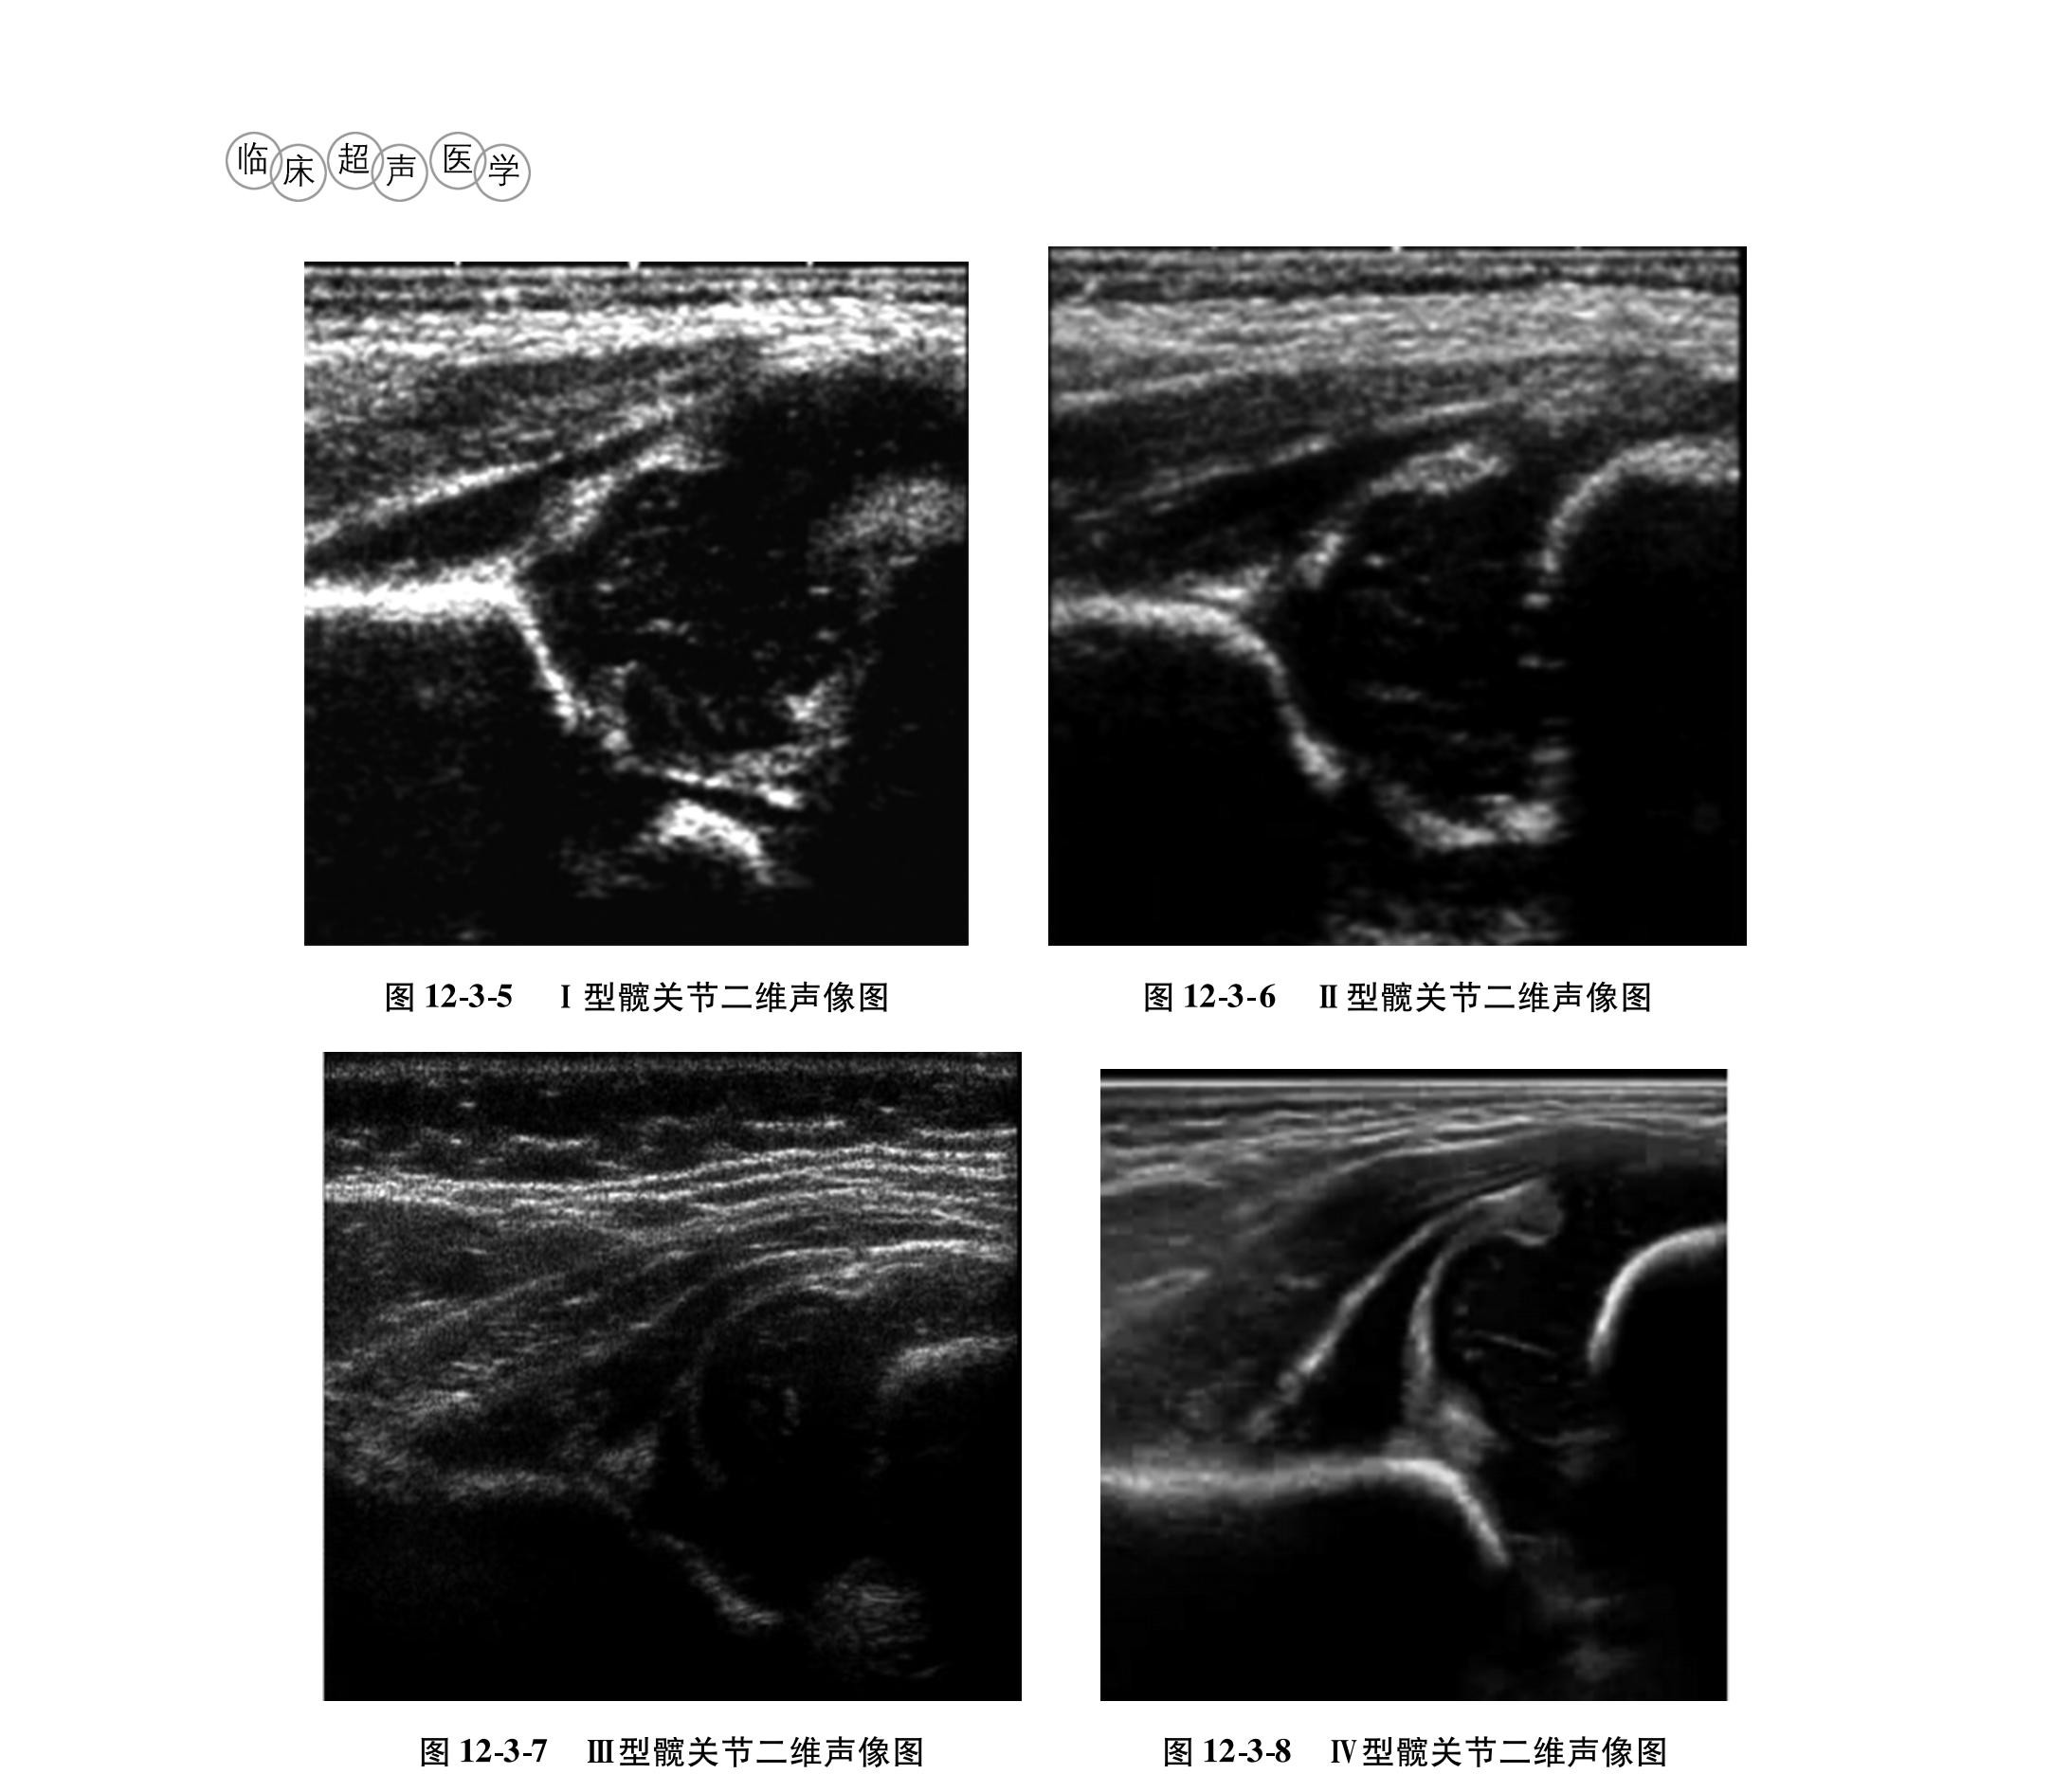

• 12.3 婴儿发育性髂关节发育不良的超声诊断

婴儿发育性髂关节发育不良的超声诊断